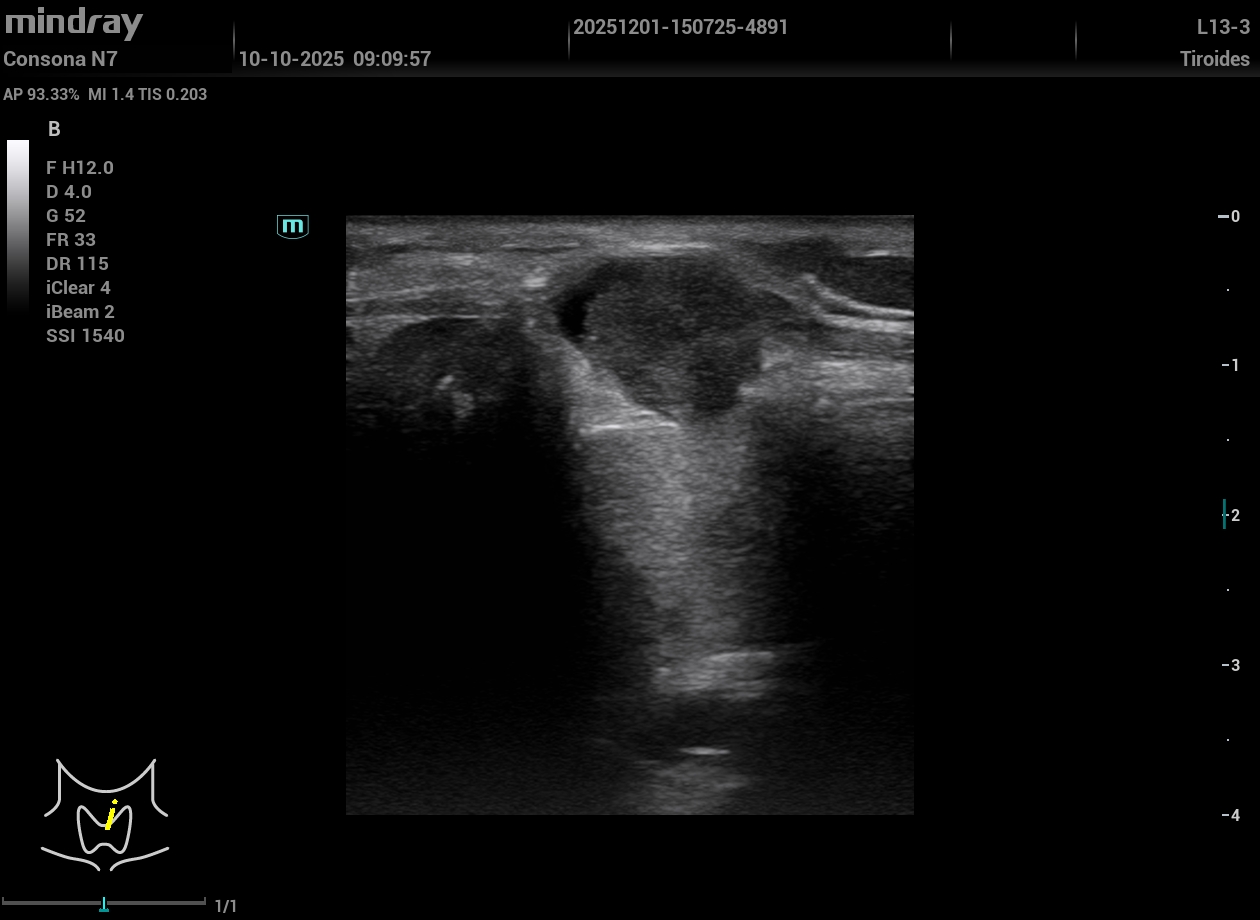

Exploración Física: Nódulo visible y palpable en línea media cervical anterior a la altura de la glándula tiroidea, no doloroso. Tras la exploración manual y dada la reciente aparición del nódulo realizamos ecografía en el momento.

Exploración ecográfica. Se observa un tiroides de tamaño y ecogenicidad normal y en istmo un nódulo hipoecogénico de aspecto heterogéneo, lobulado de bordes parcialmente delimitados, que se extiende fuera de la glándula, DE 14,3 mm de eje mayor, vascularizado y aspecto ecográfico sospechoso. TIRADS 5.

No se aprecian adenopatías patológicas.